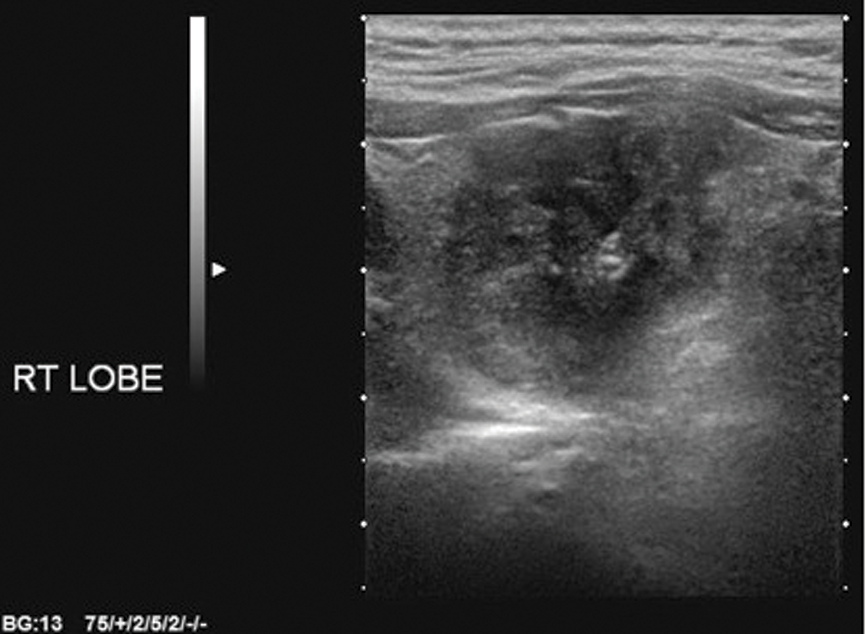

There are a few important points to consider: it is papillary cancer that is accounting for the increase in thyroid cancer incidence, and the four US features used in the Kim and AACE criteria are the cardinal features of papillary cancer (Figures 1-4). For high sensitivity, the Kim Criteria should be used, for high specificity, AACE criteria. The use of nodule size reduces sensitivity and specificity quite markedly.

Figure 2: Ill-defined margins.